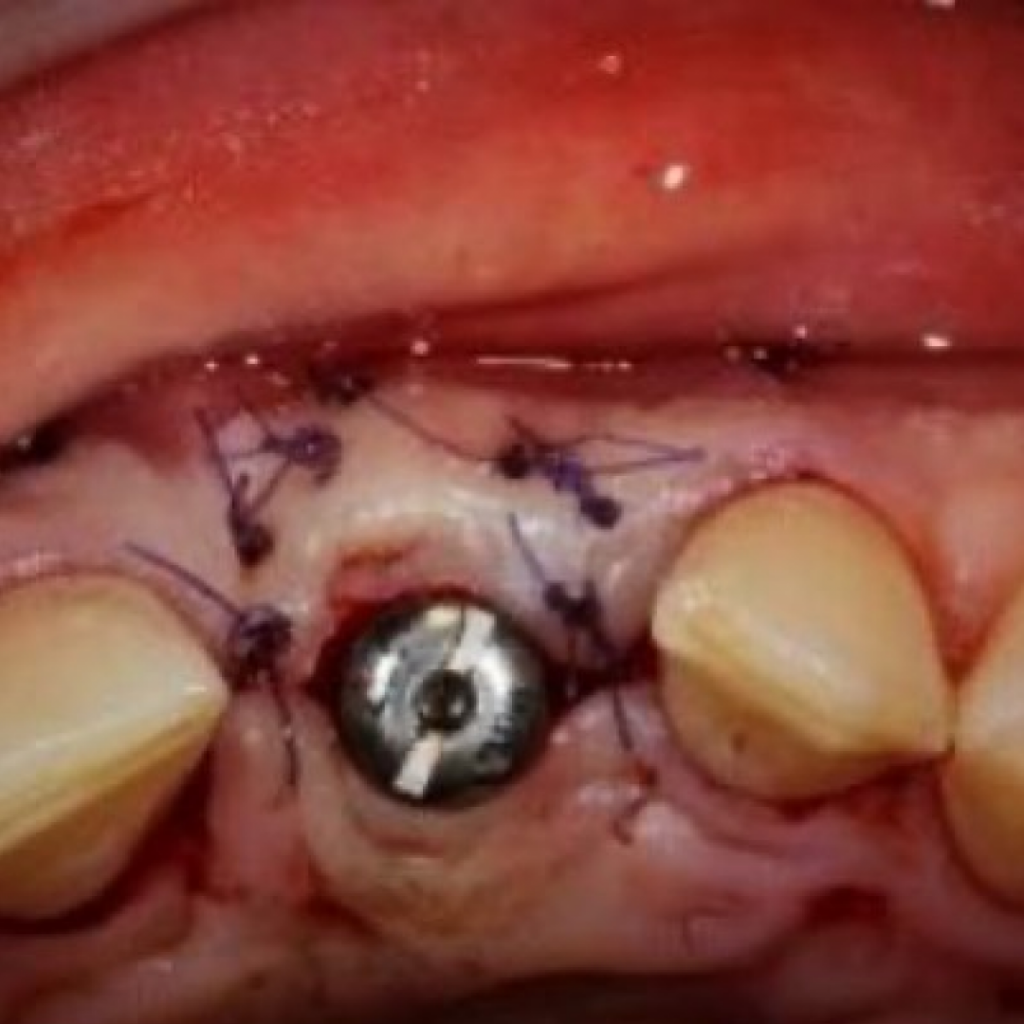

- Пациент Н. обратился с эстетическим и функциональным дефектом во фронтальной области верхней челюсти - отсутствует левый центральный резец, зуб 2.1

- Из анамнеза: в виду долгого ношения съемного протеза «бабочка», отмечается значительная атрофия костной ткани с вестибулярной стороны (со стороны верхней губы), соответственно, десневой контур также нарушен.

- Лечение: проведена дентальная имплантация AnyRidge в области зуба 2.1 с пластикой десны, а также установлена временная коронка.